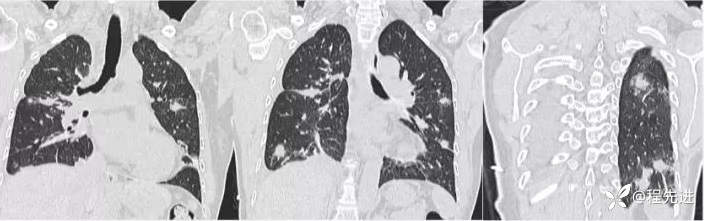

肺窗冠状位重建